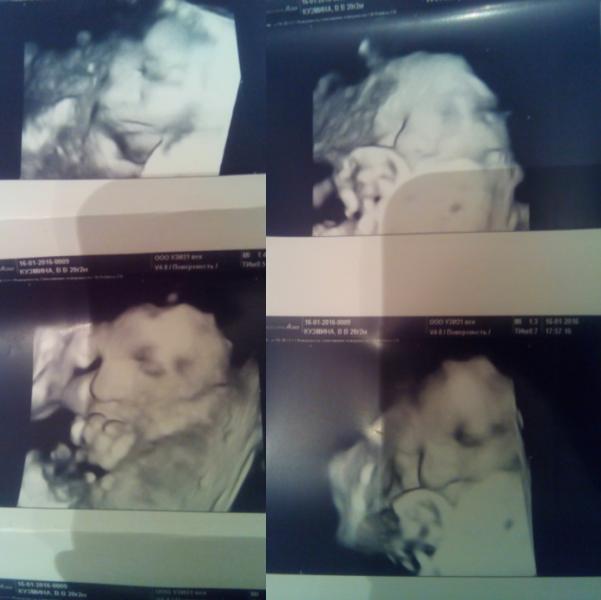

Врач понравился)В меру серьёзный,отшучивался переодически,при том внимательно осматривал и комментировал все свои действия. Сделал нам много 3D снимков нашего сына,все вылавливал момент чтобы наш упрямец убрал руку из рта)) В принципе все хорошо,кроме пары моментов.